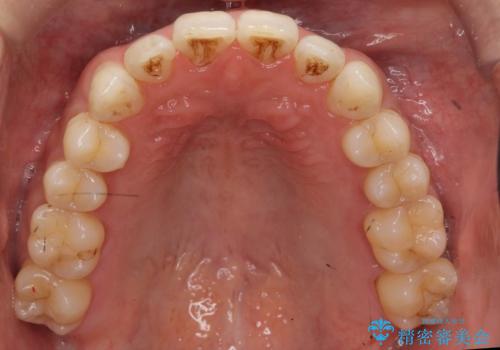

受け口 マウスピースで矯正治療 難易度:中

- 受け口を主訴に来院。

前歯の反対咬合でしたが、かみ合わせが、下顎が大きく前方にずれていました。

引っ込んでいる前歯の前方に下の犬歯が深く咬み込んでおり、また、奥歯のかみ合わせも受け口方向にずれ、骨格性の反対咬合も少々ありました。

上の前歯を前方に出すだけでは治療ができないため、ミニスクリューを用いて下の奥歯を後ろに送っています。

また、下の前歯を0.3mmずつIPRしています。

前歯の反対咬合にしては、難易度は中等度だと思います。

ちょっと前歯を外に出すだけでは治療は難しいです。

下の奥歯を後ろに送るにも、親知らずを抜いたスペース等がなければ難しいです。